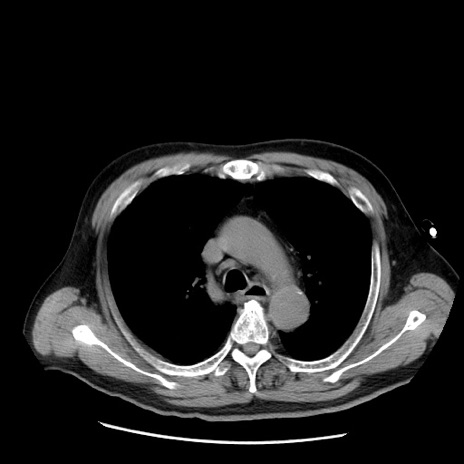

症例20(横断像)

【症例】 60歳代男性

【主訴】 腹部膨満、嘔吐

【現病歴】5日前頃より倦怠感を認め食事量減少し4日前の朝嘔吐、食事摂取困難となった。 3日前近医受診し点滴施行され整腸剤などを処方された。 当日他院を受診し、腹部膨満著明、炎症反応の上昇(CRP10.8、WBC11200)あり、紹介受診となる。

【身体所見】 意識JCS1 受け答えがはっきりしないBP 111/57mHg、 P 67bpm、、BT35.2°C、SpO2 97%(RA)、 腹部:膨隆、打診で鼓音あり、全体的に圧痛有り、腸蠕動音(-)、反跳痛ははっきりせず。

【データ】WBC 11400、CRP 14.20